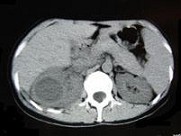

- 多项选择题女,33岁, 右肋腹痛7天,尿检可见大量的脓细胞, CT平扫+增强如图所示,下列说法正确的是 ( )

A、右肾体积增大,其内可见类圆形低密度病灶

B、增强扫描可见该病灶不均匀强化,其内有无强化的坏死灶

C、右肾病灶边界模糊不清

D、考虑为右肾囊肿合并感染

E、考虑为右肾脓肿